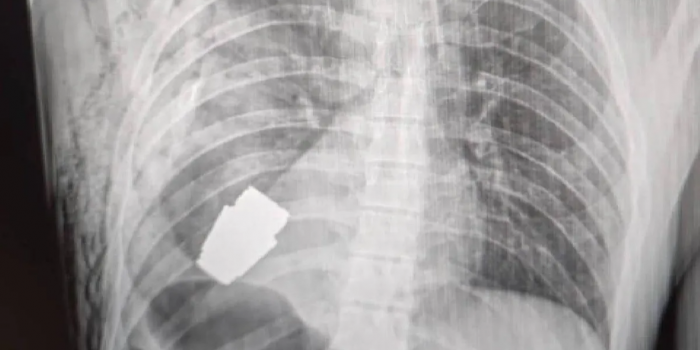

照片显示,据说一枚手榴弹被困在一名乌克兰士兵的胸部,随后医护人员将其取出。

乌克兰国防部副部长汉娜·马利亚尔在社交媒体上分享了这张x光照片。另一幅画描绘了一名外科医生戴着血淋淋的手套,仍然穿着围裙和蓬松的帽子,手里拿着一枚手榴弹。